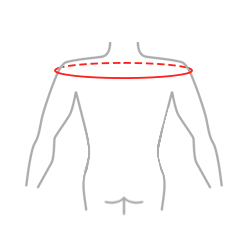

| Rozmiar | Obwód ramion na wysokości głowy kości ramiennej | Sposób dokonywania pomiaru |

| Uniwersalny | min 85 – max 95 cm |  |

| X-Size | min 95 – max 110 cm |

Całkowita długość elementu ramienia:

Uni: 22 cm

X-size: 25 cm ЗАПИСАНО